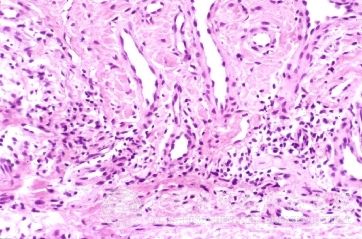

北京京城皮肤医院指出,二期梅毒树胶肿症状:二期梅毒树胶肿可发生于各个脏器,生长缓慢,可逐渐自愈,并留下瘢痕。树胶肿可分布于几乎身体的部位,但是却更常发生于小腿膝盖正下方、大腿、颜面及头皮,骨骼也可受累,引起深部刺痛,尤其在夜间疼痛更为明显。